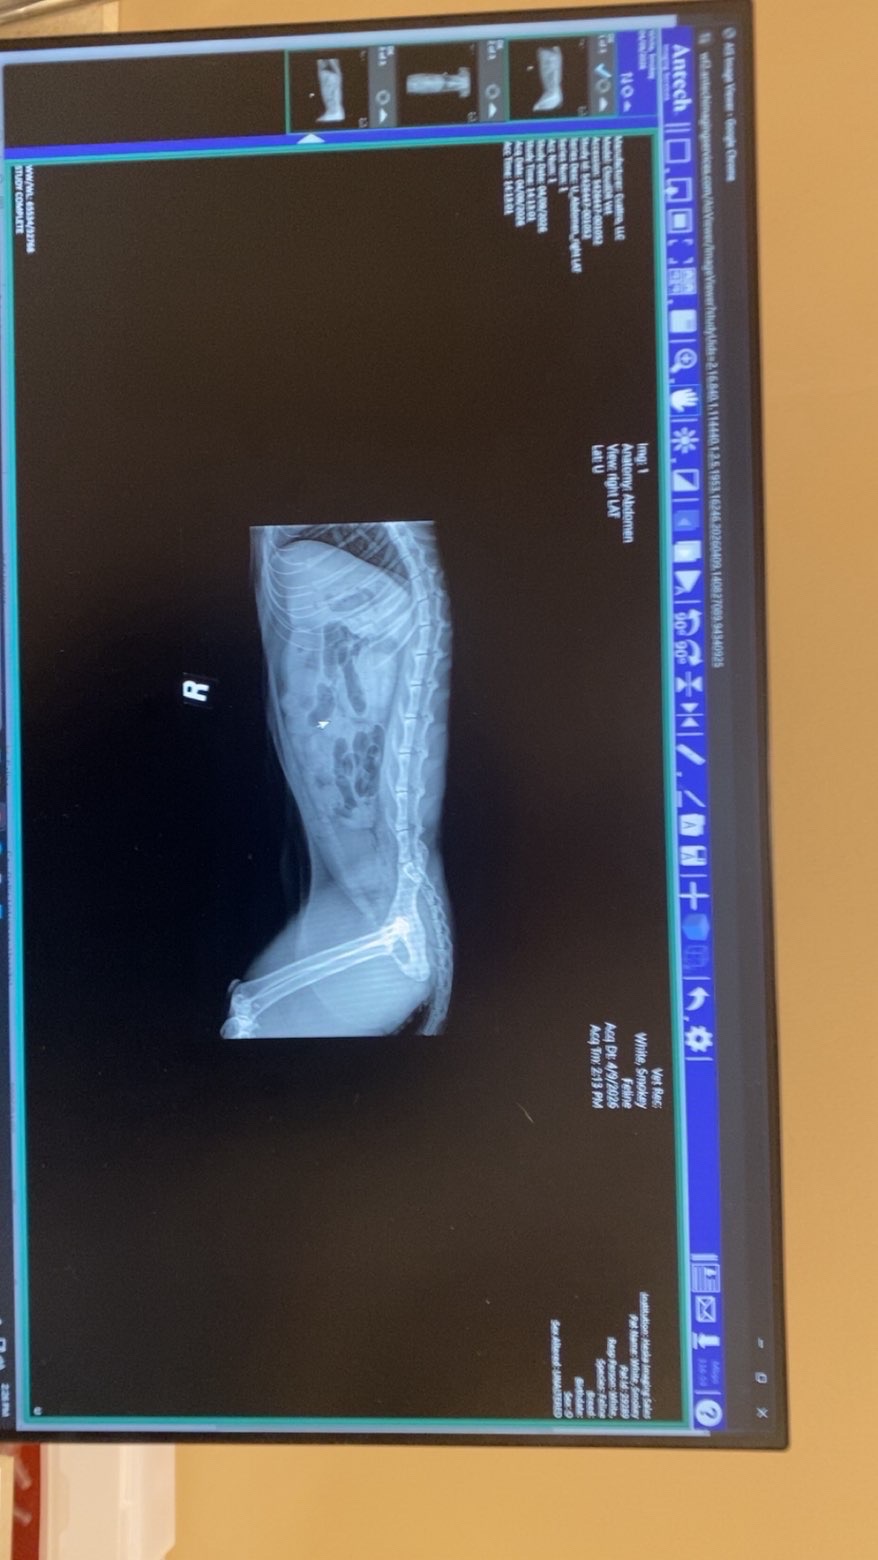

Hello, my name is Aiden, and my girlfriend Bailey and I have our cat Smokey. We took him to a pet hospital today after constant throwing up and decided to take blood work to see what was wrong. The blood work came back healthy, so we then went to a cheaper vet for X-rays for foreign body objects. We found out he has tons of abnormal gas patterns, leading to the fact that he has foreign body objects in his abdominal area. This requires surgery, and trust us when we say this surgery is NOT cheap. On the low end of things, we're looking at paying anywhere from $1,500 to $3,500 total. We love this cat with everything we have and really hope we can pull through with this money so that we can keep him and hopefully get this taken care of. Any help of any kind is GREATLY appreciated. Thank you and have a blessed day!